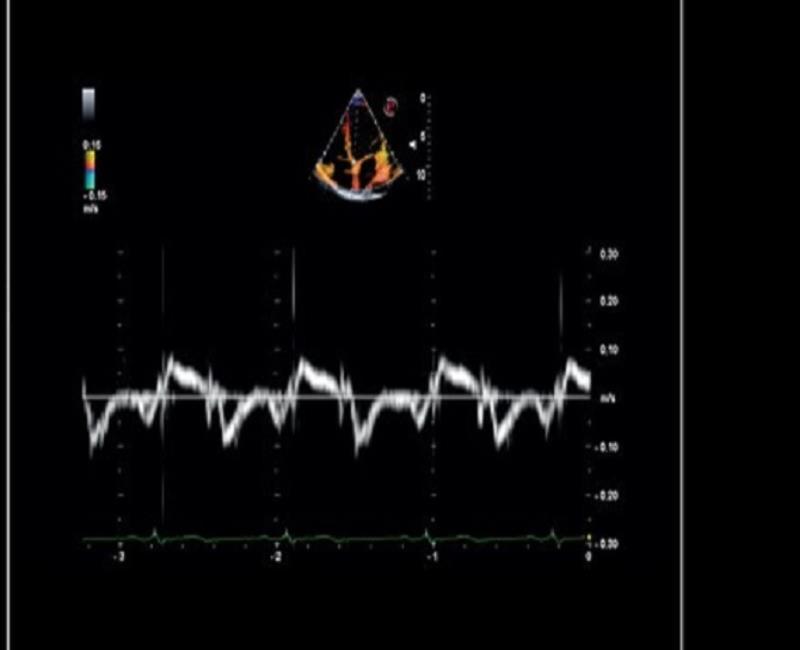

TVM - Bản đồ vận tốc mô với chế độ kép (Doppler màu và Doppler năng lượng).